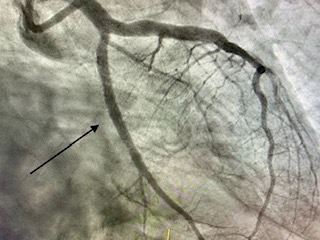

Angioplàstia amb stent

L'angioplàstia coronària transluminal percutània amb implantació de stent ha estat capaç, a les sales de RX dels laboratoris d'Hemodinàmica i Cardiologia Intervencionista, de combatre eficaçment a la malaltia que més mortalitat causa en les societats modernes: la malaltia coronària.

Angioplàstia amb stent en un infart (artèria tancada 100%)